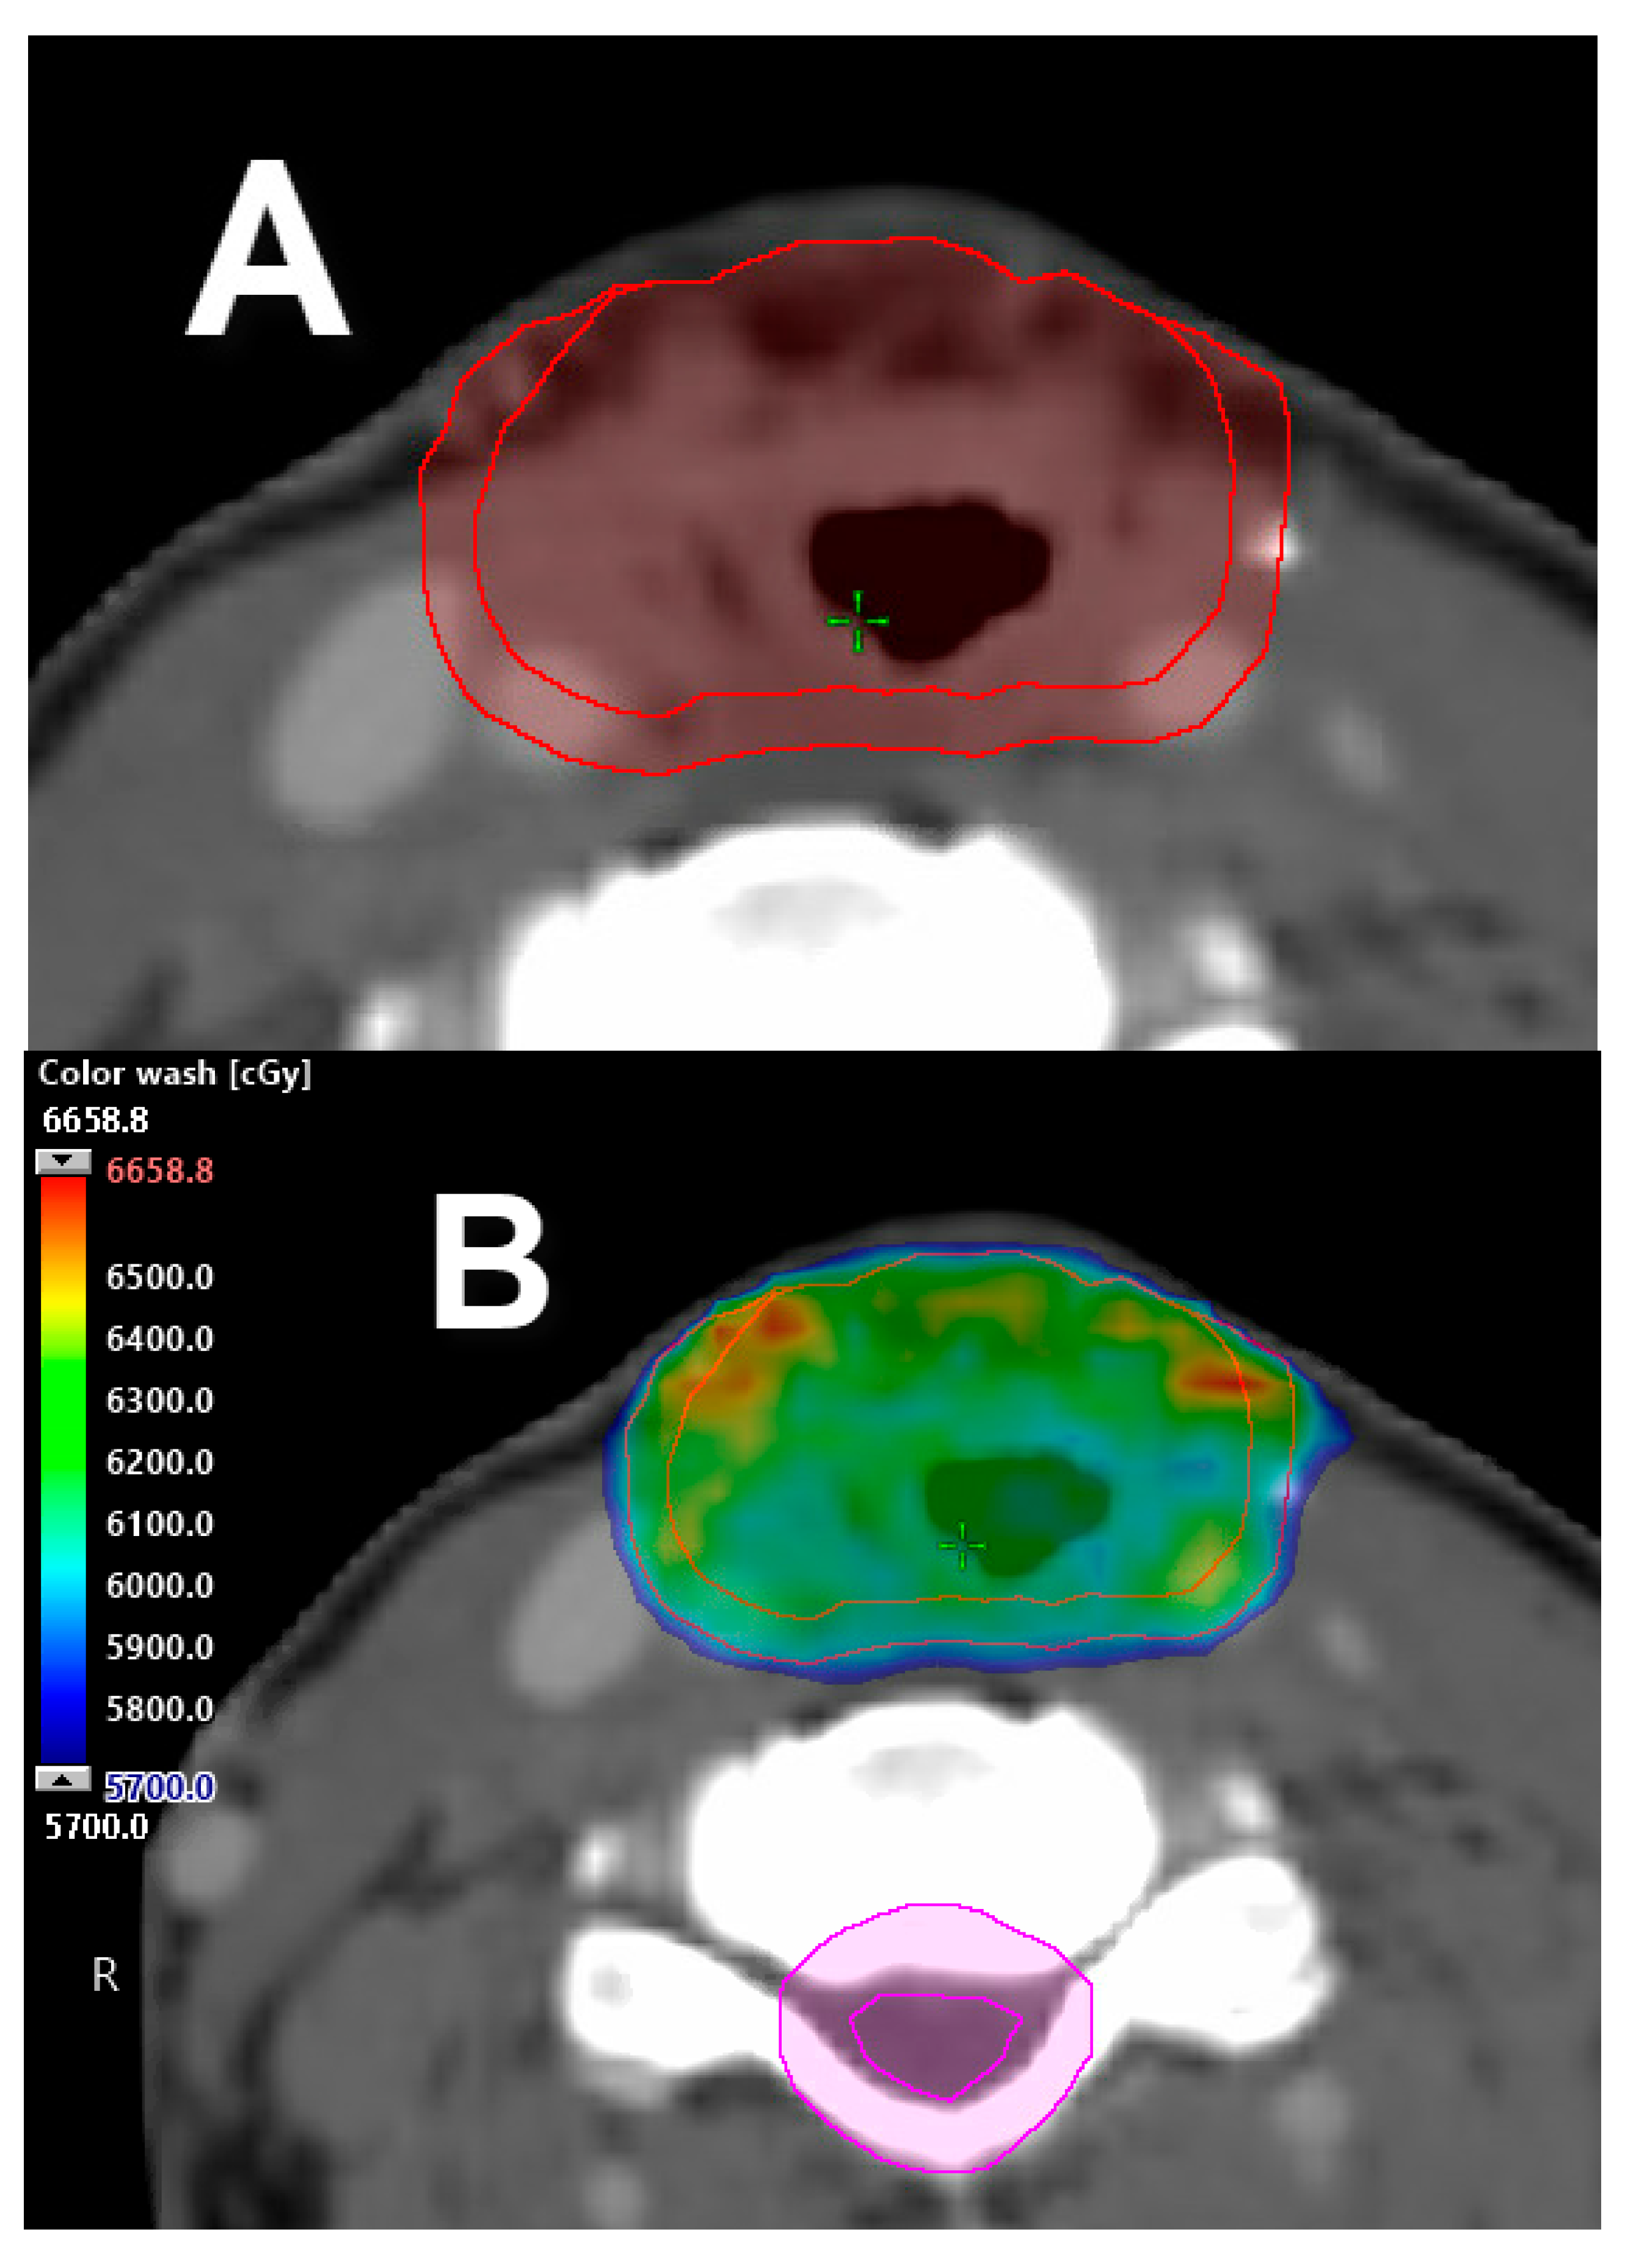

- Morgan, H.E.; Sher, D.J. Adaptive radiotherapy for head and neck cancer. Cancers Head Neck 2020, 5, 1. [Google Scholar] [CrossRef]

- Moreno, A.C.; Frank, S.J.; Garden, A.S.; Rosenthal, D.I.; Fuller, C.D.; Gunn, G.B.; Reddy, J.P.; Morrison, W.H.; Williamson, T.D.; Holliday, E.B.; et al. Intensity modulated proton therapy (IMPT)—The future of IMRT for head and neck cancer. Oral Oncol. 2019, 88, 66–74. [Google Scholar] [CrossRef]

- Anand, A.; Bues, M.; Gamez, M.E.; Stefan, C.; Patel, S.H. Individual field simultaneous optimization (IFSO) in spot scanning proton therapy of head and neck cancers. Med. Dosim. 2019, 44, 375–378. [Google Scholar] [CrossRef]